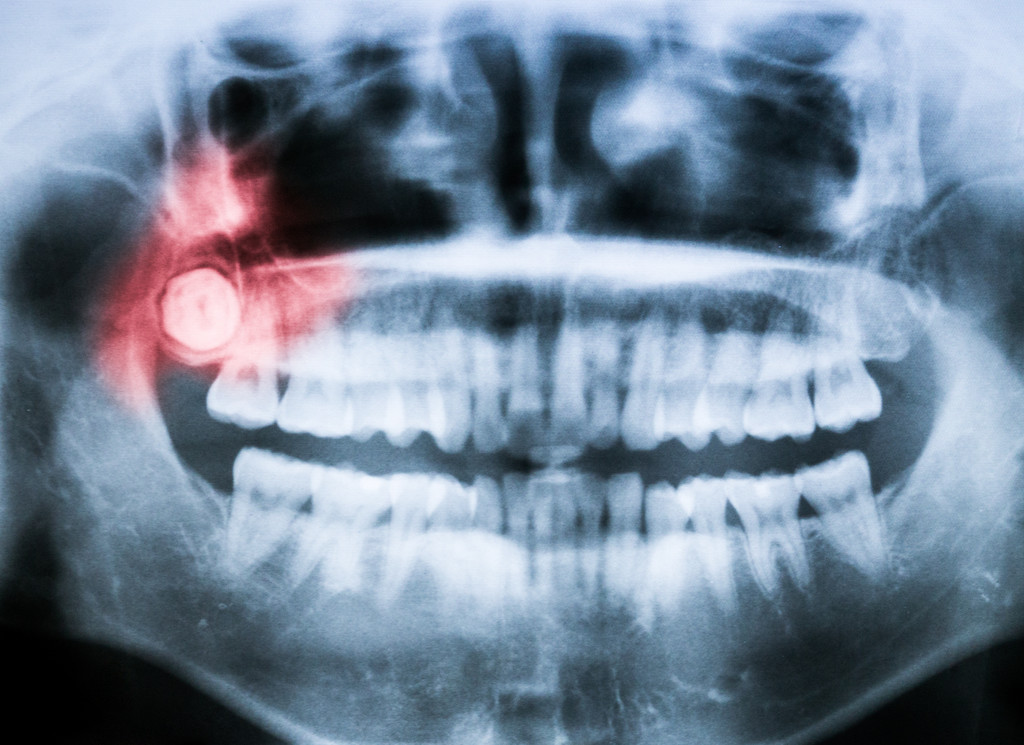

What Are Wisdom Teeth And Why Are They Removed . getting your wisdom teeth removed is almost a rite of passage for young adults. wisdom tooth removal recovery. wisdom tooth removal surgery is a common dental procedure used to extract teeth from the third set of molars, called your wisdom. some dentists recommend removing wisdom teeth if they don't fully grow in. But do you really need the. Wisdom teeth may cause complications that get worse over time. wisdom teeth are the third and final set of molars that most people get in their late teens or early twenties. Why do we have wisdom teeth? Wisdom tooth extractions are one of the most common surgeries young adults undergo. why do wisdom teeth get removed? why are wisdom teeth removed? Teeth are categorized by their placement and function. In many instances, taking out.